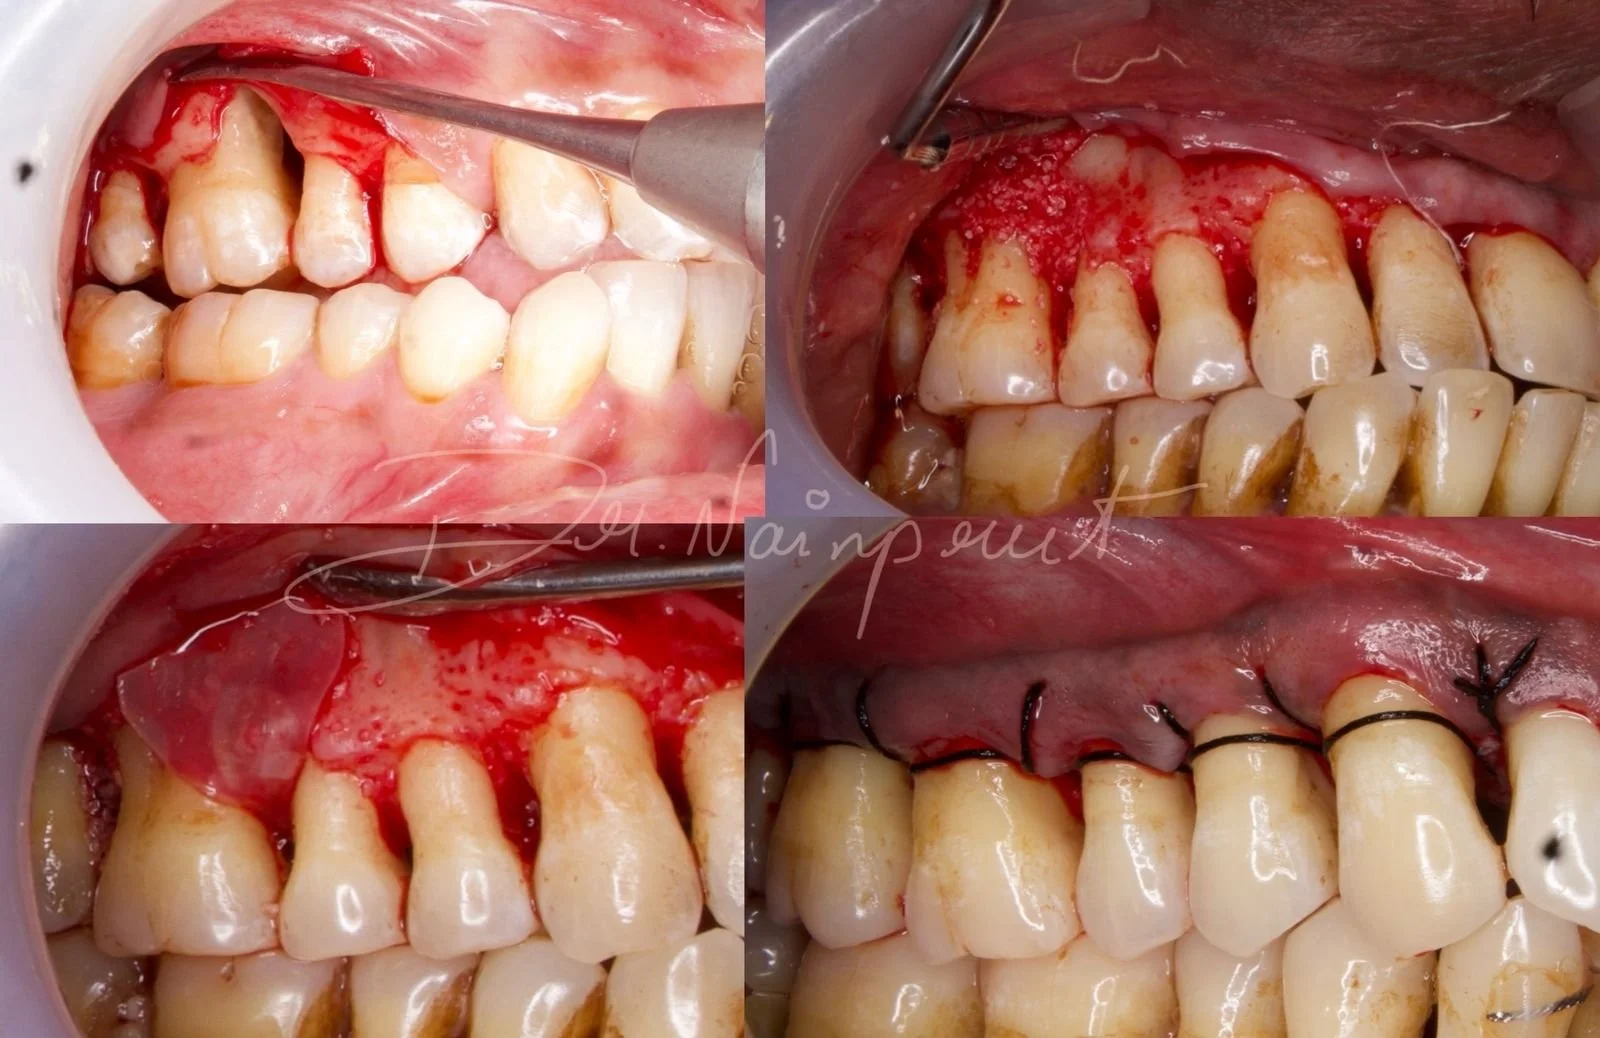

Root coverage with Tunelling and coronally advanced flap

Case done by Dr NIvedha, III year PG